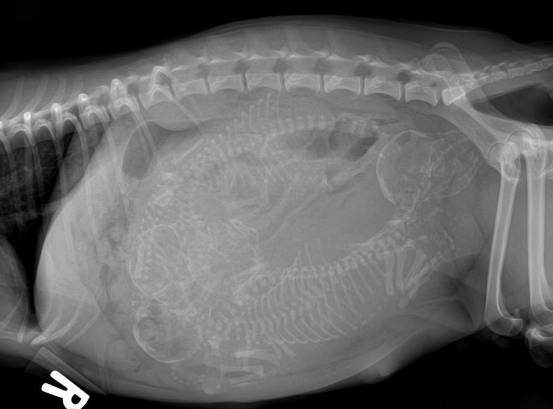

在猫咪的怀孕后期,在第六周和第七周的时候,胚胎已经发育完好,成型为幼猫了。